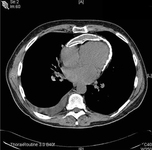

Tomografia computadorizada (TC) do tórax mostrando uma camada dupla de calcificação pericárdica em um paciente do sexo masculino de 56 anos de idade com pericardite constritiva idiopática com calcificações

Patanwala I, Crilley J, Trewby PN. BMJ Case Reports 2009; doi:10.1136/bcr.06.2008.0015